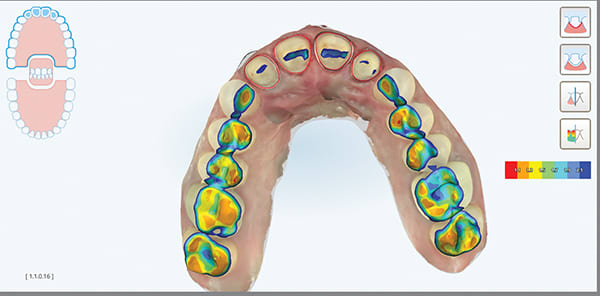

A female patient aged 57 years presented with altered passive eruption of the maxillary anterior teeth, which was diagnosed as a secondary condition to tooth erosion resulting from long-standing gastroesophageal reflux disease (GERD). Clear aligner therapy was initiated to level and align the occlusion and intrude the maxillary anterior teeth back to their original gingival position. After 18 months of poor patient compliance, improvement in tooth position was minimal and the amount of clinical overjet that was desired was not achieved. This limited the restorative armamentarium, and a decision was made to proceed with monolithic zirconia-oxide restorations. Following teeth preparation and tissue retraction, the case was impressed using an intraoral scanner (iTero® Element 2, Align Technology, Inc., itero.com). The final restorations were made of zirconium dioxide with a feldspar veneering ceramic shade 1M1 as the pressed layer on porcelain on the facials. The outcome of the case met the patient's primary concerns, achieving the lengthening and lightening of the anterior teeth that she desired. Because of the patient's continued challenges with GERD, however, she reported having difficulty with compliance related to the clear aligner therapy and whitening protocols, precluding a more ideal result. Nonetheless, the patient was pleased with her new smile and the clinician, given the challenging circumstances, was satisfied with the clinical results of the final restorations.

A key component of the zirconia-based treatment for this case was the use of an intraoral scanner for digital impressions, which allowed for clear marginal visualization, time efficiency, and a simplified impression process.

Digital impressions are an effective, predictable alternative to conventional impression techniques and may be considered as the first option for impression-taking.